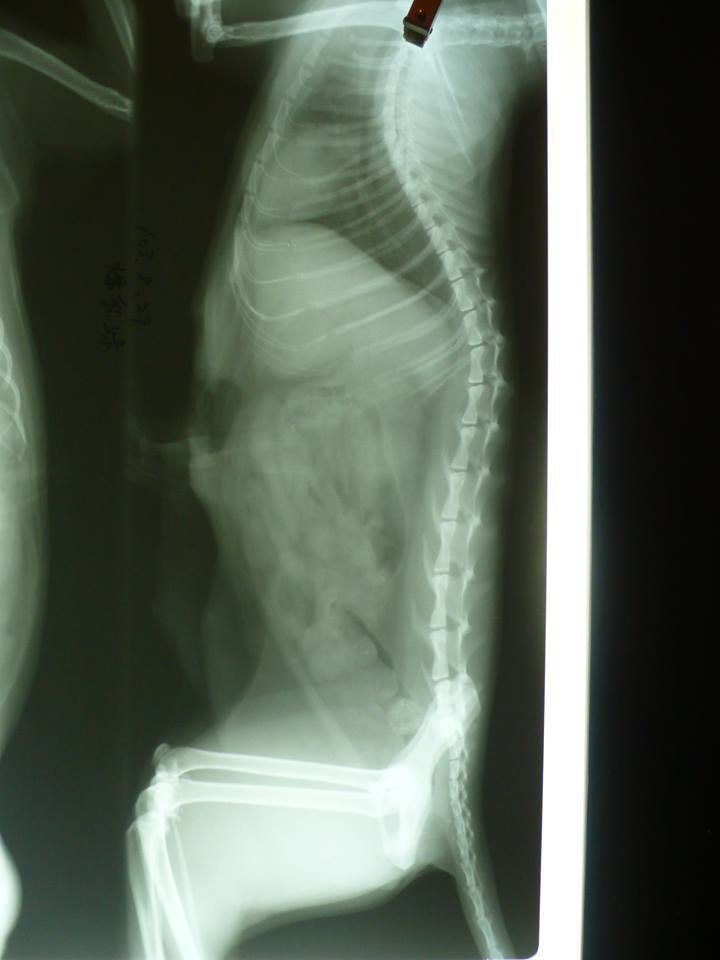

主題: 乳頭破一個大洞 申請者姓名: 陳曉霏 花色: 申請日期: 2014-10-23 03:52:53 申請者部落格: 申請者臉書網址: 所在縣市/合作醫院: 台北市/長沁動物醫院 治療費用: 19956元 需求人數: 23人 已結案 (2014-11-12 11:55:52) 報名人員: Sa Hsu(已付款)、悅萱 x3(已付款)、Jelly Lee(已付款)、米雪路(已付款)、ARu Lin(已付款)、Rocky Chen x3(已付款)、Dahany(已付款)、Salome Chang(已付款)、vivian(已付款)、小黃(已付款)、肥仔(已付款)、Momo Liao x2(已付款)、FS.NG(已付款)、莊珍妮 x2(已付款)、Bubu Dai x2(已付款)、Larisa Lee(已付款)、 候補人員: 動物病情說明: 親人的三花媽媽

沒想到醫生一檢查 才發現傷口很大

因為已經都感染

醫生先將乳線切除

其餘傷口部份先清創

也怕有腫瘤的疑慮

將部份組織先送驗

所幸結果是好的

因為這次手術範圍很大

因手術較為複雜 費用也不低